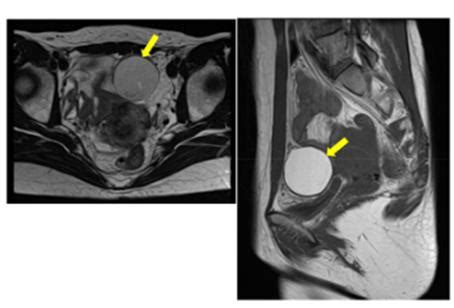

子宫内膜异位症与不孕 正常妇女不孕率约为l5%,内膜异位症患者可高达40%。重度子宫内膜异位患者不育的原因可能与盆腔内器官和组织广泛粘连和输卵管蠕动减弱,以致影响卵子的排出、摄取和受精卵的运行有关。但盆腔解剖无明显异常的轻症患者亦可继发不育不育的原因绝非单纯局部解剖异常所致。现多认为异位内膜患者的不育还可能与以下因素有关: 1) 黄体期功能不足:内膜异位症患者卵泡和黄体细胞上的LH受体数量较正常妇女为少,以致黄体期黄体分泌不足而影响受孕。网址: www.hyfymz.com 2) 黄素化未破裂卵泡综合此病征为卵巢无排卵,但卵泡细胞黄素化,患者虽体温呈双相,子宫内膜显示分泌期,但无受孕可能。其诊断依据是在腹腔镜检查下,在应有的排卵期后4一l0日,卵巢表面末见排卵孔;在LH高峰后2日,检查时,卵泡仍继续生长;月经周期中,腹腔液量特别是腹腔液中雌激素和孕激素“无突发性增高。有报告证实内膜异位症患者LUFS的发生率较正常妇女显著增高,并发不孕。Konincks则提出由于LUFS的存在,腹腔液中雌、孕激素水平低下,不抑制逆流至腹腔内的内膜细胞种植,因而导致盆腔内膜异位症,故认为LUFS正是膜异位症的发病原因。但此学说尚未为人们所承认。 3)自身免疫反应:内膜异位症患者体内B淋巴细胞所产生的抗子宫内膜抗体可干扰早期受精卵的输送和着床,腹腔内巨噬细胞增多亦可吞噬精子和干扰卵细胞的分裂从而导致不孕。